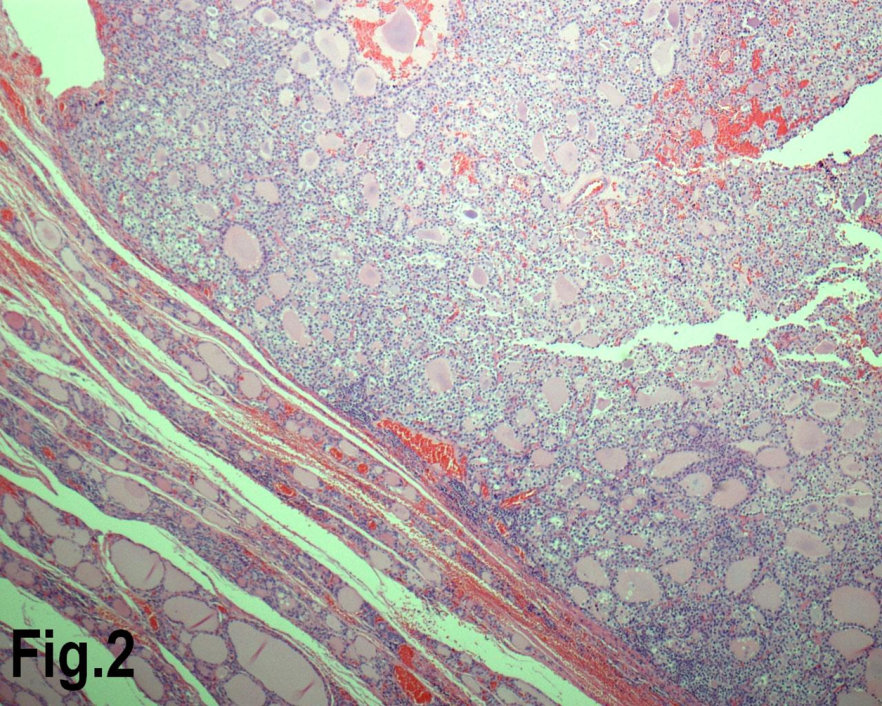

Solitary benign adenomas were found in 23 cases, the peak frequency was fourth and fifth decade. Female accounted for 12 cases (70.5%) for follicular adenoma (Figure 2) and 3 cases (50%) for Hurthle cell adenoma. Thyroid malignancy and it was reported in 62 cases. Papillary carcinoma (Figure 3) was the most common type of thyroid malignancy found in 44 cases (71%) followed by follicular carcinoma (9.6%) (Figure 4), medullary carcinoma (1.6) and poorly differentiated carcinoma (1.6%) (Table 3). The peak incidence for patients with thyroid malignancy in this series was third decade and male to female ratio was 3.7:1.

Figure 2.Low power view showing a follicular adenoma. (Hematoxylin & eosin, original magnification ×200).